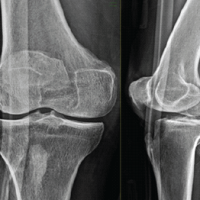

A 32-year-old male presented with pain in the left knee with stiffness for 1 year following a history of twisting injury to the knee while walking. He gave a history of locking episodes and difficulty in squatting and sitting cross-legged. He was a known case of chronic gout for 3 years on irregular medication. His father was a known case of Gout and was on treatment for 25 years. On examination, the patient had ichthyosis over both legs since childhood and mild effusion over the knee, with lateral joint line tenderness and a flexion deformity of 20°. The knee was stable without laxity, with a range of motion (ROM) from 20° to 70°, which was painful. (Fig. 1).

He had no other palpable gouty lesion in the body. He had an elevated serum uric acid of 13.4, with other normal blood parameters. The patient had a pre-operative Lysholm knee score of 35/100. MRI revealed Arthrofibrosis with lateral meniscal tear with mucoid degeneration of anterior cruciate ligament (ACL) with synovitis. The report did not mention any evidence of chondrocalcinosis. Due to the patient’s chronicity of mechanical symptoms and meniscal tear, the patient was taken up for diagnostic arthroscopy. The arthroscopic examination revealed synovitis with widespread chalky deposits over the chondral surfaces, menisci, fat pad, ACL and synovium in the suprapatellar pouch and intra-articularly. (Fig. 2).